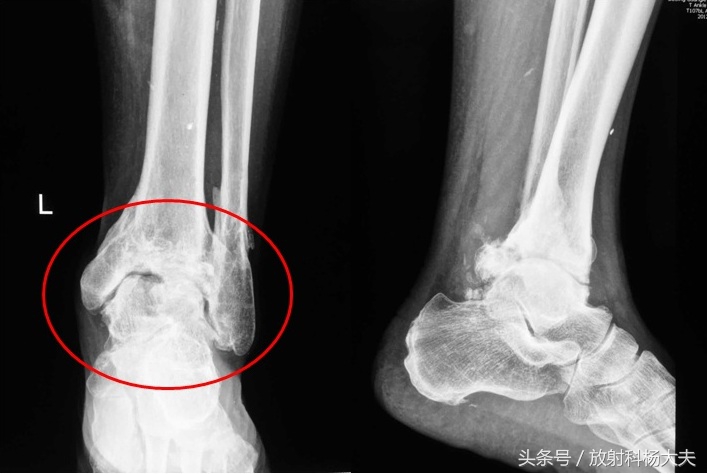

原来老王有一个朋友,是一位工地工作的工人,一位五十余岁的中年男性,工作过程中不小心砸伤了左踝,自己认为体力劳动中磕磕碰碰在所难免,自觉无大碍便没有前来就医,心里想着伤筋动骨一百天,忍忍疼,平时自己再注意些就好了。这一搁置就是两年,两年间自己的左踝关节,反复的疼痛,每次肿痛就自己用点药,过阵子好了继续干活,逐渐的,左踝越来越“胖”,甚至穿高腰的鞋子都难受。看着自己“变胖了”的踝关节再也回不去了,并时常疼痛且酸软无力,在家人的催促下,去拍了片子, “创伤性骨关节病”。所谓骨关节病,其实就是骨关节的一种退变。膝关节更常见,从关节软骨损伤开始,逐渐出现关节间隙变窄,骨刺等,严重的疼痛严重,生活不能自理,需要做膝关节置换手术。但如果是创伤后发生的,病变会更严重,关节增生、骨质碎裂,比普通的退变严重的多。老王的朋友因为两年前开始的损伤,没能及时就诊,现在不用说工地干活赚钱,甚至已经严重影响生活,追悔莫及也没有用。或许两年前的某个瞬间,他也想去医院拍个片子,但毕竟错过了。

创伤性骨关节病,踝关节明显变胖